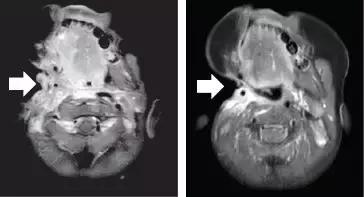

昨天关于第二代TRK靶向药物的论文刚刚发表,最初的两位耐药患者尝试新药后,肿瘤再次快速缩小。比如下面这位,用药一个月后,耐药的肿瘤就再次几乎消失!

耐药后 使用2代药一个月后